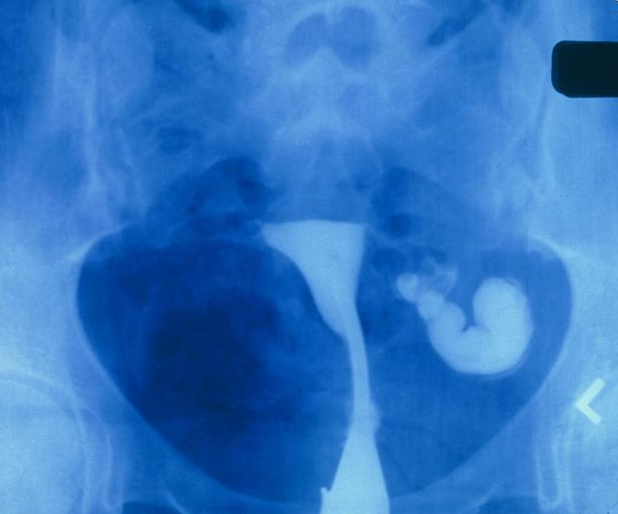

不過,造影雖然是通過X射線直觀診斷,但也需要通過導管在女性宮腔和輸卵管內注入液體,如碘水或碘油,也會有一些疼痛感。

一般來說,造影檢查分為:傳統碘油造影和無痛碘水造影。前者,檢查時會有一定的疼痛,檢查后建議避孕3個月再試孕;后者,無痛、對輸卵管傷害小,造影劑可吸收,做完檢查下個月就能試孕。

一般來說,做子宮輸卵管造影所使用的手段都可能會有不同,但不管是哪些方式,都會使用到X線照射操作。雖然在醫學臨床上,并沒有女性在子宮輸卵管造影后當月懷孕就會增加胎兒異常的幾率這種言論的證明。但是,很多醫生都會建議女性在做輸卵管造影3個月后再受孕,盡可能的減少X線照射帶來的影響。同時,在備孕前要做好孕前檢查。當然,因為輸卵管造影的方式不同,所產生的影響也不同,具體的還是需要詢問醫生再做決定。